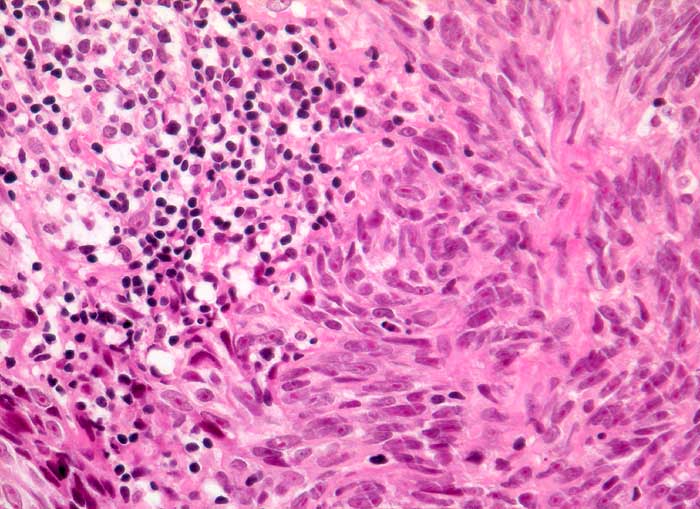

Lymphknotenmetastase: Malignes Melanom

Melanome metastasieren häufig in die Lymphknoten. Sie können morphologisch sehr unterschiedlich aussehen. Melanome erscheinen zytologisch teils wie ein Sarkom, teils wie ein Karzinom. Die Tumorzellen können Pseudoverbände ähnlich einem Karzinom bilden. In zellreichen Aspiraten erkennt man oft Kapillarachsen, denen die Tumorzellen in mehreren sich gegen peripher auflockernden Schichten anliegen, so dass ein garbenartiges Muster entsteht, wie man es auch bei Sarkomen beobachten kann. Prominente Nukleolen und intranukleäre Vakuolen sind oft vorhanden. Melanotische Metastasen sind aufgrund des Melaninpigmentes leicht diagnostizierbar. Bei amelanotischen Metastasen kann eine immunzytochemische Untersuchung mit S-100 und/oder HMB-45 weiterhelfen.